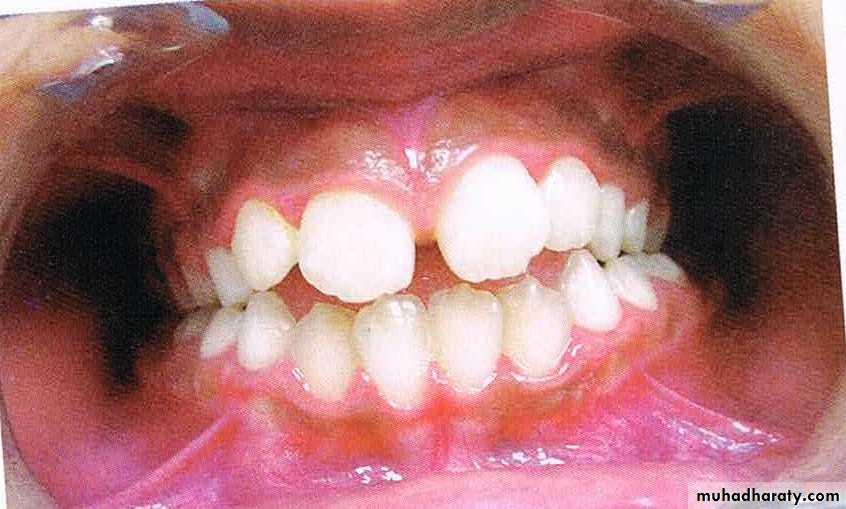

Dental Crowding

Definitioncrowding is a condition where there is malalignment of teeth caused by inadequate space

Crowding: lack of space for a permanent tooth to erupt. Those teeth that erupt last in segment, e.g. lateral incisors, upper canines, 2nd premolars, 3rdmolars are most commonly affected

Crowding of teeth